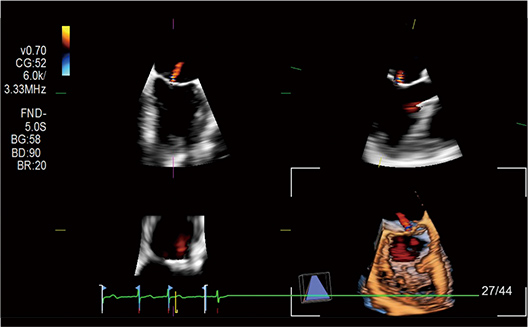

A validated application that demonstrates blood flow patterns in the heart in a new way. From one cine loop, flow direction without angle dependency, vorticity, energy loss, wall shear stress and relative pressure can all be appraised. Wall Shear Stress (WSS) can be applied to blood vessels as well.